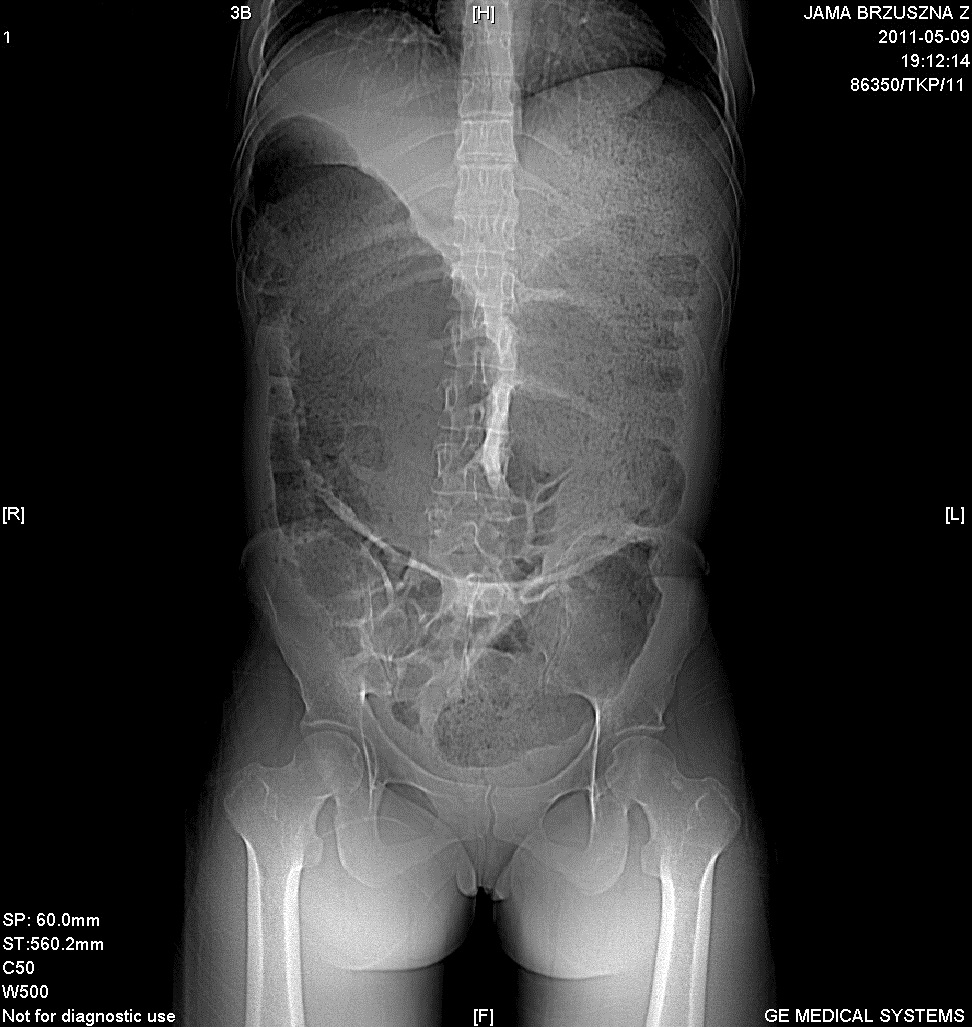

TK jamy brzusznej   uwidoczniono masywne poszerzenie jelita grubegoAutorzy przedstawiają 31–letnią kobietę, która zgłosiła się do szpitala z powodu bólów brzucha, wzdęcia oraz zatrzymania gazów i stolca. W przeszłości była dwukrotnie operowana z powodu endometriozy zlokalizowanej w jajnikach w 2007 i 2010 r. W tomografii komputerowej jamy brzusznej uwidoczniono guz zgięcia esiczoodbytniczego. Wykonano operację Hartmanna. Badanie histopatologiczne wyciętego jelita wykazało, iż guz zamykający światło jelita spowodowany był przez endometriozę. Po 15 dniach chora została wypisana w stanie ogólnym dobrym. Po 12 miesiącach odtworzono ciągłość przewodu pokarmowego.

The authors present a 31-year-old woman who presented to the hospital with abdominal pain, bloating and gas and stool retention. She had been operated on twice in the past for endometriosis located in the ovaries in 2007 and 2010. An abdominal CT scan showed a tumor of the sigmoid flexure. Hartmann's surgery was performed. Histopathological examination of the resected bowel showed that the tumor closing the lumen of the bowel was caused by endometriosis. After 15 days, the patient was discharged in general good condition. general well. After 12 months, the continuity of the gastrointestinal tract was restored.